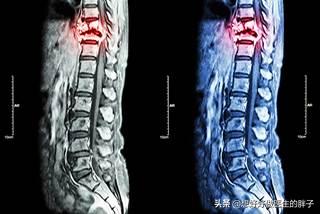

Imagerie par résonance magnétique des métastases osseuses

Montrant un cancer avec métastases osseuses survenant dans la colonne vertébrale thoracique